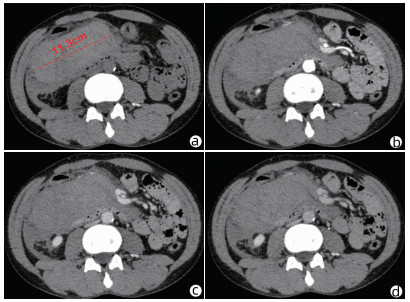

Clinical effect of simultaneous surgical resection of hepatic and pancreatic lesions versus systemic chemotherapy in treatment of resectable pancreatic cancer with liver metastasis

Tianqiang JIN, Chaoliu DAI, Feng XU

2022, 38(3): 622-628. DOI: 10.3969/j.issn.1001-5256.2022.03.023

Abstract(1500) HTML (1256) PDF (2734KB)(76)

Abstract:

Objective  To investigate the clinical effect of simultaneous surgical resection of hepatic and pancreatic lesions versus systemic chemotherapy in treatment of resectable pancreatic cancer with liver metastasis (PCLM).  Methods  A retrospective analysis was performed for related data of the patients with PCLM who were admitted to Shengjing Hospital of China Medical University from January 2013 to May 2020, and the patients with resectable PCLM were screened out and then divided into surgery group and chemotherapy group. The propensity score matching (PSM) method was used to reduce the impact of data bias and confounding factors. The independent samples t-test or the Mann- Whitney U test was used for comparison of continuous data between two groups, and the chi-square test was used for comparison of categorical data between two groups. The Kaplan-Meier method was used to calculate survival time, and the log-rank test was used for evaluation. The univariate and multivariate Cox regression models were used to investigate the independent risk factors for survival.  Results  A total of 56 patients with resectable PCLM were screened out, with 33 patients in the surgery group and 23 patients in the chemotherapy group, and there were 15 patients in each group after PSM. The surgery group had a significantly shorter median overall survival time than the chemotherapy group before PSM (6.6 months vs 10.4 months, χ2=4.476, P=0.034) and after PSM (6.4 months vs 10.5 months, χ2=4.309, P=0.038). The multivariate Cox regression analysis showed that poorly differentiated tumor (hazard ratio [HR]=4.945, 95% confidence interval [CI]: 1.980-12.348, P=0.001) and absence of postoperative chemotherapy (HR=3.670, 95%CI: 1.437-9.376, P=0.007) were independent risk factors for poor prognosis in patients with PCLM.  Conclusion  Compared with chemotherapy, simultaneous surgical resection of hepatic and pancreatic lesions fails to prolong the overall survival time of patients with resectable PCLM. Patients with poorly differentiated tumor and those without postoperative chemotherapy tend to have poor prognosis.